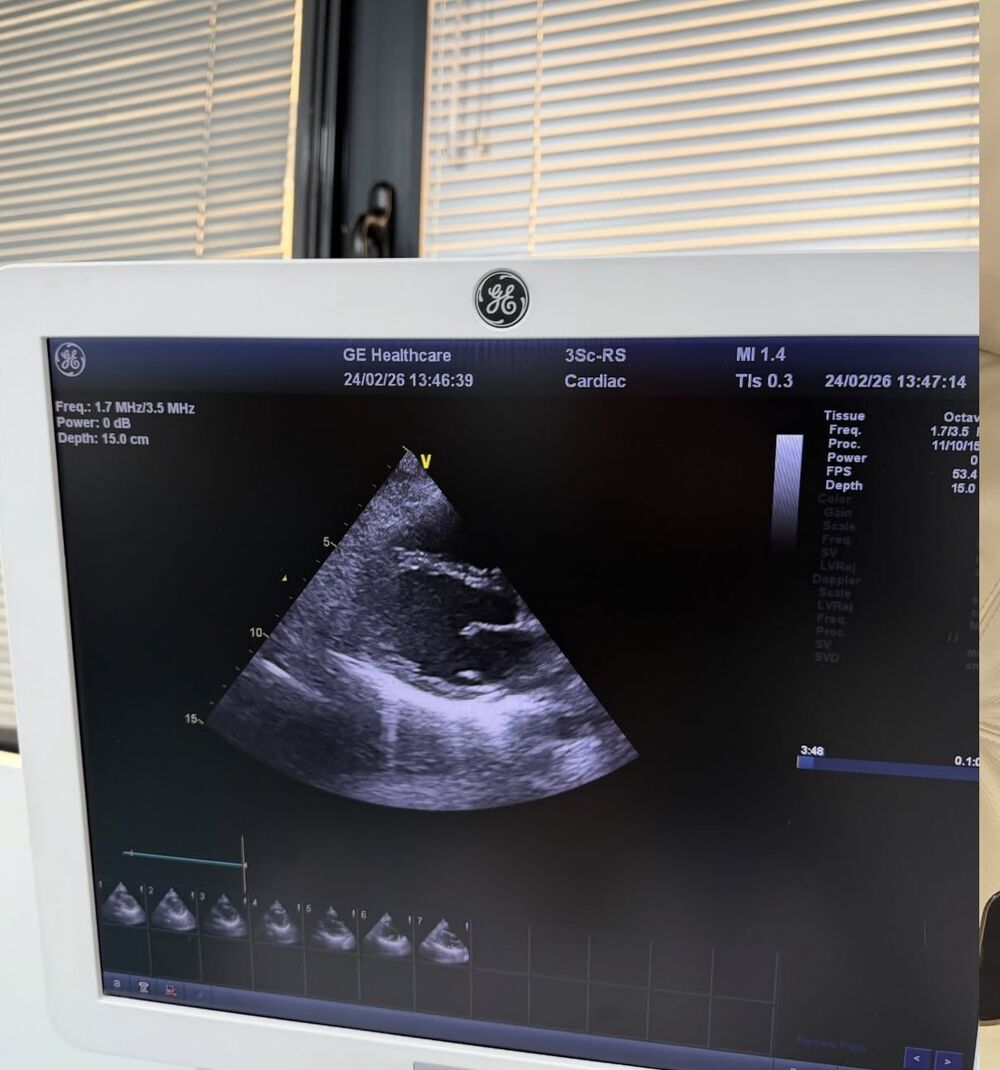

• Subakutni perikarditis: Zapaljenje srčane maramice izazvano virusom.

"Želela sam ovo da podelim kako bi moji fanovi razumeli zašto me nije bilo. Nadam se brzom oporavku i povratku karijeri koju najviše volim," napisala je ona uz fotografiju sa Holter monitoringom i aparatima za pritisak.